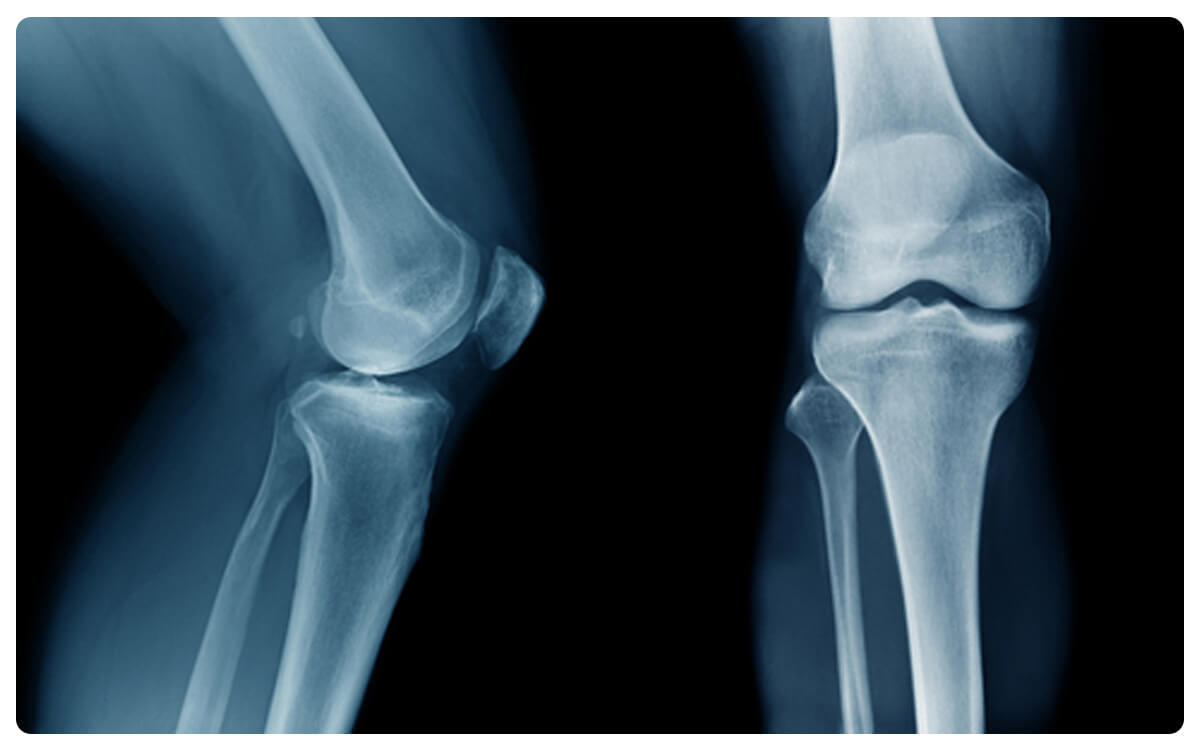

La Radiografía de Pierna en Proyección Anteroposterior (AP) de la Tibia y el Peroné se establece como una herramienta esencial en la radiología diagnóstica, ofreciendo una visión detallada y estructurada de la anatomía y posibles afecciones de esta región anatómica. A través de la emisión controlada de radiación, esta técnica no invasiva proporciona imágenes bidimensionales que permiten la evaluación de los huesos de la pierna, especialmente la tibia y el peroné, desde una perspectiva frontal.

La Radiografía de Pierna en Proyección AP desempeña un papel crucial en la detección y diagnóstico de fracturas,

desplazamientos, malformaciones óseas y otras patologías que afectan esta zona, proporcionando información valiosa para

la toma de decisiones clínicas informadas y el manejo adecuado de las afecciones relacionadas con la pierna.